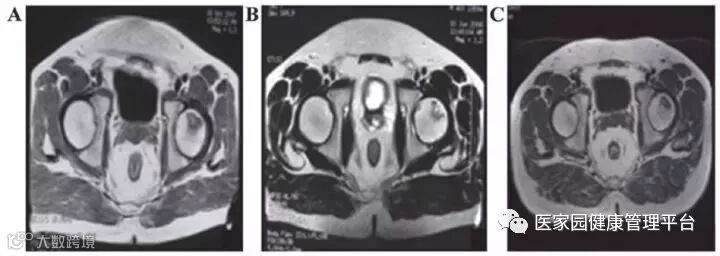

脐带MSC治疗股骨头坏死的临床研究结果